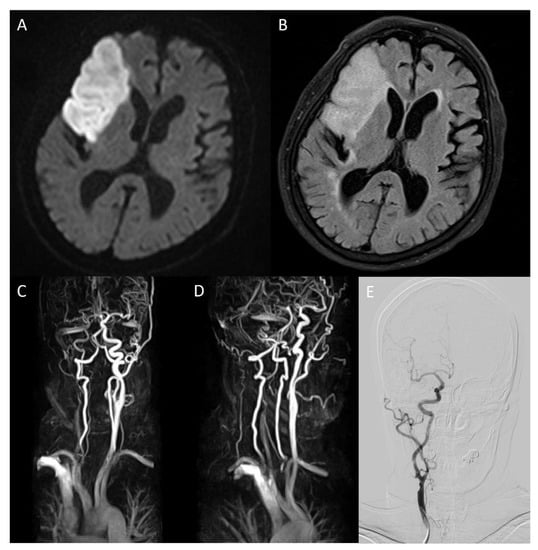

An 86-year-old female patient visited the emergency room complaining of left hemiparesis on waking. This occurred 30 h before her hospital visit. The patient was diagnosed with hypertension 10 years ago and was on medication. She was also diagnosed with hyperlipidemia but refused to take the medication. A neurological examination was performed immediately. The patient exhibited facial palsy, left hemiparesis, and dysarthria. The National Institute of Health Stroke Scale (NIHSS) score was 4, and mental status was alert. Electrocardiography demonstrated atrial fibrillation. The chest radiography revealed cardiomegaly. Brain magnetic resonance (MR) diffusion-weighted imaging (DWI) and fluid-attenuated inversion recovery (FLAIR) detected high-intensity signals suggestive of acute infarction in the right middle cerebral artery (MCA) territory (Figure 1A,B). Severe stenosis of the right internal carotid artery (ICA) was also confirmed on MR angiography (Figure 1C). Laboratory results indicated increased LDL cholesterol (190 mg/dL), total cholesterol (277 mg/dL), and triglyceride (253 mg/dL). Lowered HDL cholesterol (36.4 mg/dL) was also shown in the results. Other laboratory results were normal. The patient was prescribed dual antiplatelet agents (aspirin and clopidogrel) and statin (rosuvastatin 20 mg/day) on admission.

Figure 1.

On brain magnetic resonance diffusion-weighted image (DWI) conducted after admission, infarction in middle cerebral artery territory was confirmed (A). On fluid-attenuated inversion recovery, high-intensity signals in the same area were detected (B). Magnetic resonance angiography (MRA) showed severe stenosis ranging from the right carotid bulb to the right ICA, causing decreased blood flow to the brain ((C), arrow). The overall state of the carotid bulb and ICA was examined through sagittal rotation of MRA (D). Spontaneous regression of former severe stenosis to mild degrees was confirmed on right ICA angiography of digital subtraction angiography on hospitalization day 16 (E).

On the eighth day of hospitalization, the patient complained of dyspnea. Pleural effusion in the right lung was confirmed by follow-up chest X-ray, and the management for pleural effusion was initiated. On the eleventh day of hospitalization, carotid duplex ultrasonography showed extensive stenosis from the right carotid artery bulb to the proximal ICA (Figure 2). Peak systolic velocity (PSV) measured at the site of ICA stenosis was 214.4 cm/s, indicating moderate to severe grade stenosis (Figure 2). Although the patient needed (DSA) and carotid artery stenting to manage the symptomatic CAS, these procedures were delayed to the sixteenth day of hospitalization because of her aggravated general condition due to pleural effusion. On the right ICA angiogram of the DSA, the previously confirmed moderate to severe stenosis had almost regressed. Only mild stenosis with ulcerative plaque was observed (Figure 1D, 15% of the North American Symptomatic Carotid Endarterectomy Trial, NASCET). Therefore, carotid stenting was not performed, and we focused on acute stroke management. There were no additional lesions on the follow-up MRI. The patient was subsequently discharged without significant problems. One month after discharge, the patient’s lipid profile improved and the results are as follows: LDL cholesterol (116 mg/dL), total cholesterol (195 mg/dL), triglyceride (155 mg/dL), and HDL cholesterol (48 mg/dL).